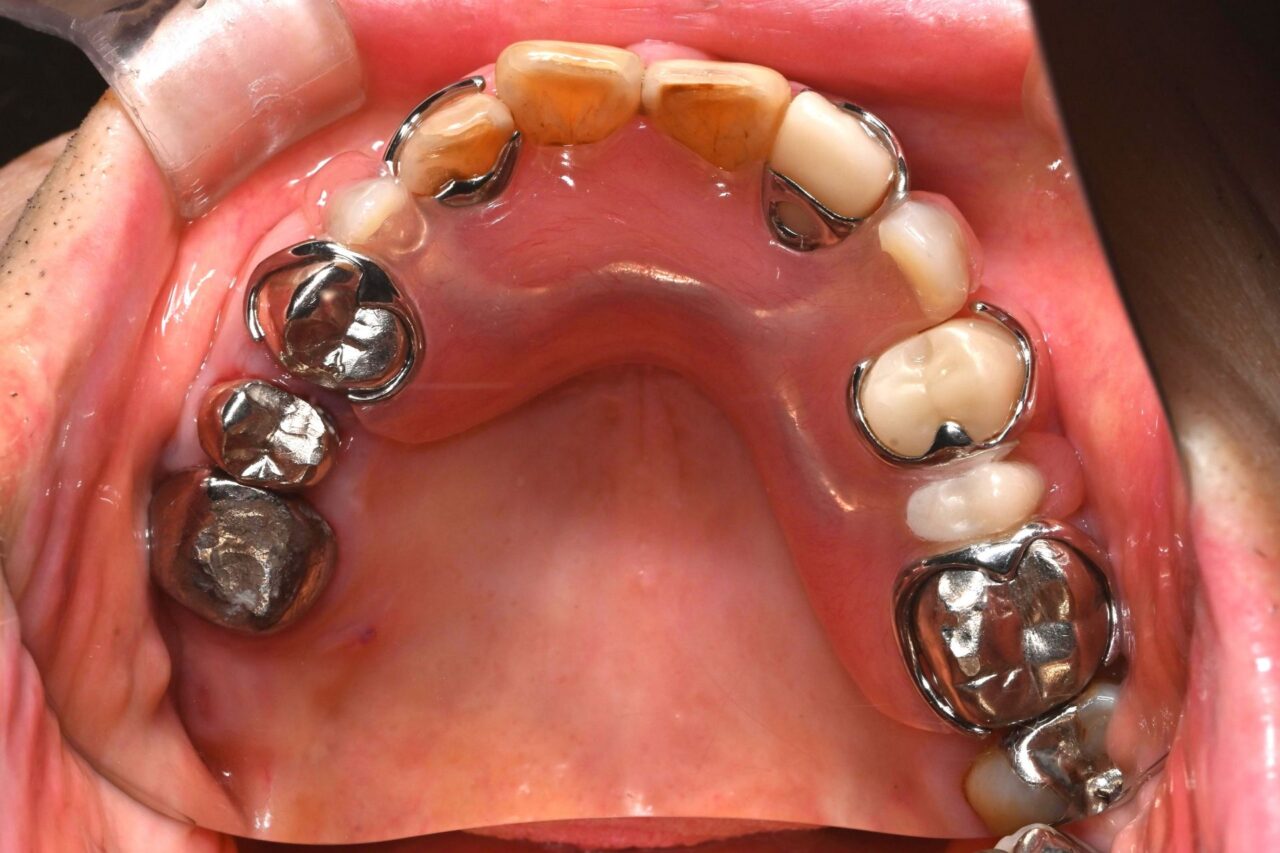

上面

虫歯を放置して残根状態です。このような歯を放置すると命の危険にさらされます。

最小限の入れ歯にして、咬合を復活させました。